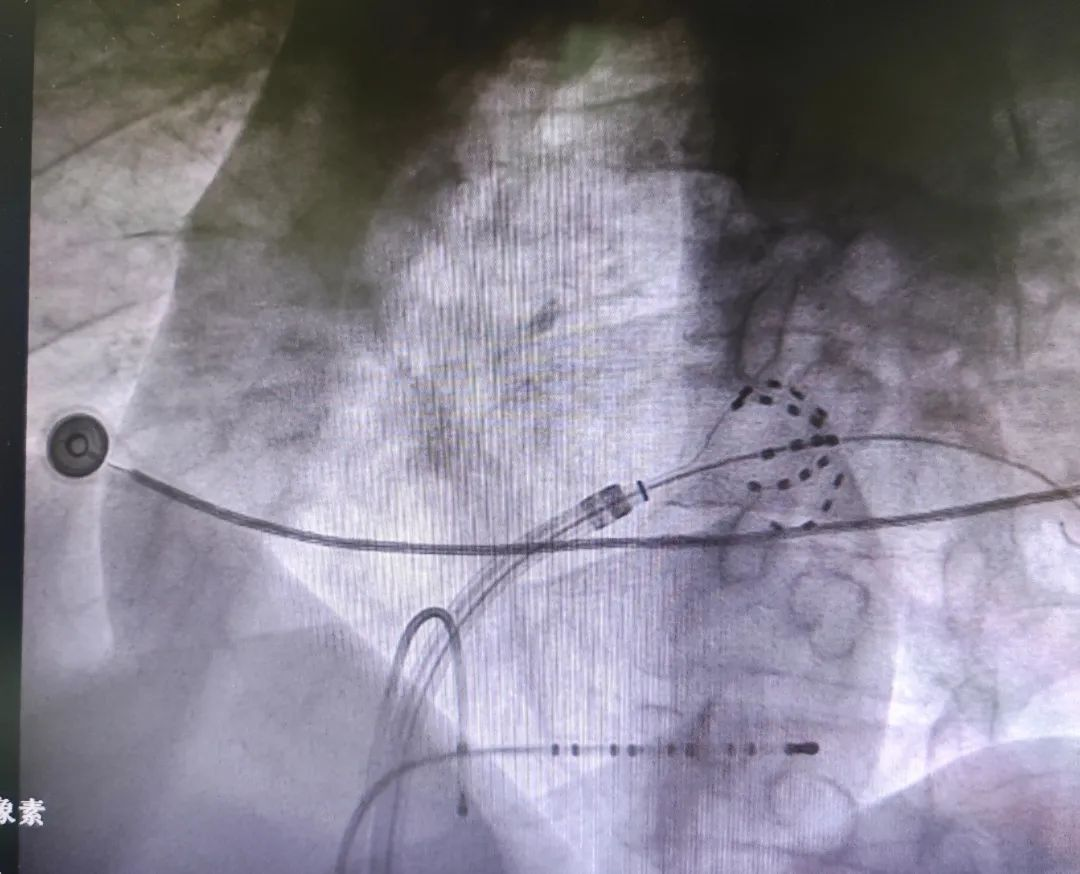

患者在全麻状态下,穿刺右侧股静脉,置入冠状窦电极及鞘管,DSA下完成房间隔穿刺。术中采用国际前沿的FARAPULSE™脉冲消融导管,依次对左侧上下肺静脉及右侧上下肺静脉进行消融。消融过程包括对肺静脉口部及前庭区域,分别以网篮状和花瓣状消融方式各进行4次消融 ,累计消融 32次。术后通过起搏验证,确认肺静脉均已成功隔离,手术圆满成功,全程消融及操作耗时仅21分钟,在手术效果得以保证的同时,极大提升手术效率,降低术者手术时间。

DSA下FARAPULSE导管呈网篮状态

DSA下FARAPULSE导管呈花键状态